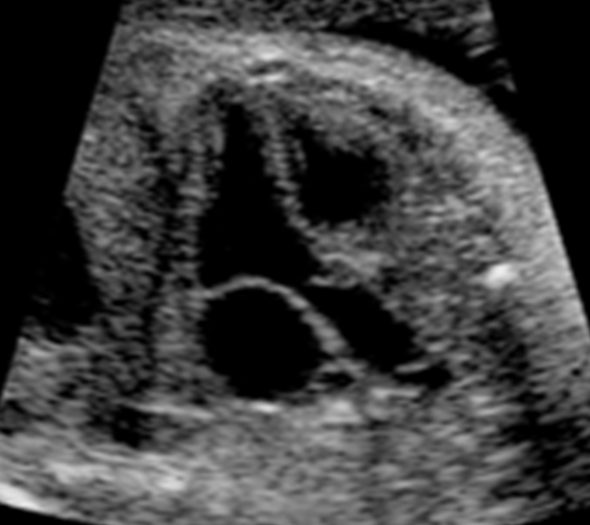

What view is this?

Long-axis Outflow Tract/ LVOT

LVOT / Long axis